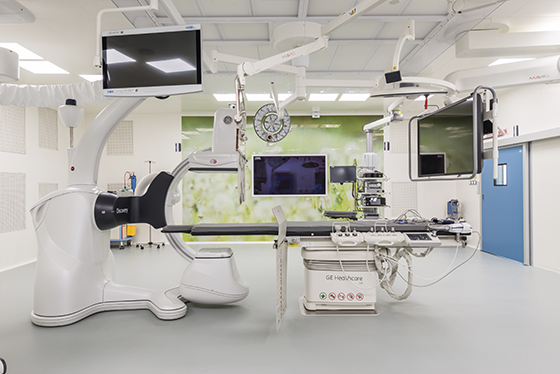

В институте онкологии Hadassah Medical Moscow создана группа специалистов по лечению различных онкологических заболеваний под руководством врача-онколога, к.м.н, директора отдела клинических исследований Утяшева И.А. Особое внимание в нашей работе уделяется диагностике и лечению аденокарциномы легкого — одного из наиболее распространенных онкозаболеваний. В этой статье мы рассмотрим основные аспекты этого заболевания и подходы к его лечению в нашем медицинском центре.

Лечение аденокарциномы легкого в клинике Hadassah Medical Moscow отличается современным и комплексным подходом. Преимущества нашей клиники включают:

Клиника Hadassah Medical Moscow предоставляет пациентам доступ к передовым методам диагностики и лечения аденокарциномы легкого. Мы понимаем, как важна поддержка и профессиональный уход на каждом этапе борьбы с болезнью. Поэтому в нашей клинике созданы все условия для того, чтобы обеспечить пациентам комфортное лечение и реабилитацию.

В Hadassah Medical Moscow наша главная цель – обеспечить каждому пациенту наилучший шанс на выздоровление и возвращение к полноценной жизни. Врачи в Хадассе всегда стремятся к максимально индивидуализированному подходу, учитывая все особенности заболевания и пациента.